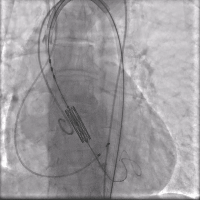

手术采用科凯生命科学自主研发的KoKaValve®经导管主动脉瓣膜系统,其瓣膜特点为短支架球囊扩张瓣膜设计,采用14F可扩张鞘管,从而适应更细的外周血管结构,此次手术采用26mm球囊扩张瓣膜,选择左侧股动脉为辅入路,右侧股动脉为主入路,颈内静脉植入临时起搏器,右侧股动脉植入14F可扩张鞘管,建立通路,跨瓣膜并植入Amplaz Super Stiff支撑导丝,采用配套23mm扩张球囊预扩张(视频1)。

预扩张(视频1)

经过14F可扩张鞘输送26mm瓣膜至降主动脉,回撤瓣膜至输送器球囊部,采用可调弯输送系统过弓并精确定位于主动脉瓣膜(视频2)。

定位 (视频2)